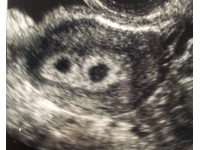

PREGNANCY IN GOATS

There is nothing more rewarding than seeing an animal that you have carefully and lovingly reared start on her own journey of rearing young and goats are no exception. If you are intending to breed your goat/goats then here is a brief explanation of what to expect throughout the doe’s pregnancy.